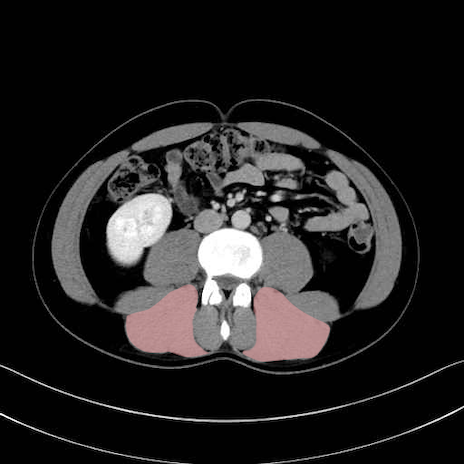

脊柱起立筋 (Erector spinae)

多裂筋 (Multifidus)

2. 腸腰筋群と骨盤底筋

大腰筋 (Psoas major)

腸骨筋 (Iliacus)